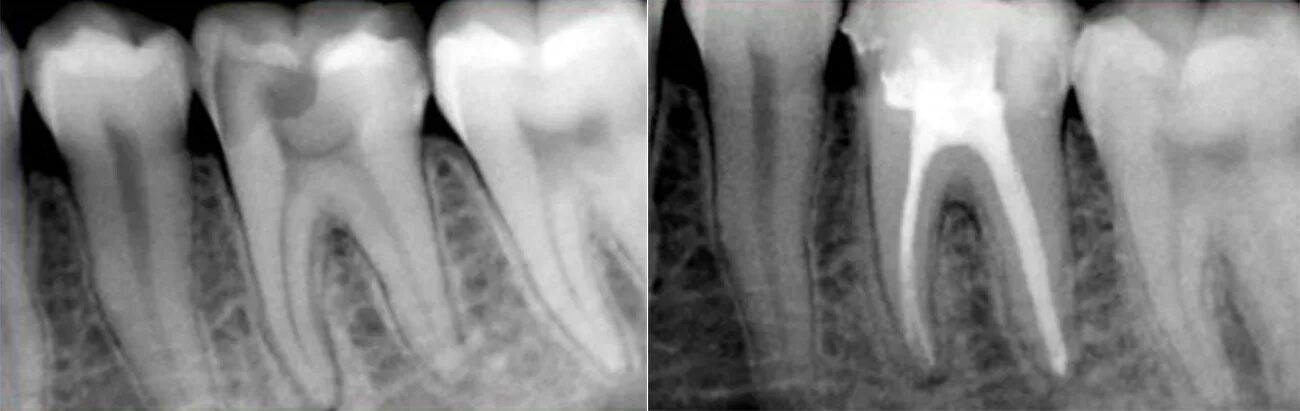

Обтурация корневого канала рентген. пульпит 17 зуба рентген с запломбированными каналами. пломбировка каналов зуба рентген.

Снимок запломбированного зуба. снимок запломбированных каналов.

Пломбировка каналов зуба.